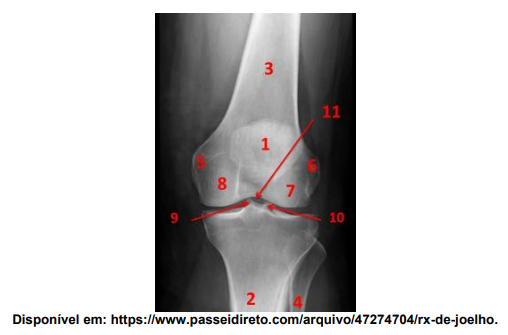

Analise a figura:

Neste raio-X do joelho representado, assinale a alternativa que indique o achado anatômico presente no número 7: